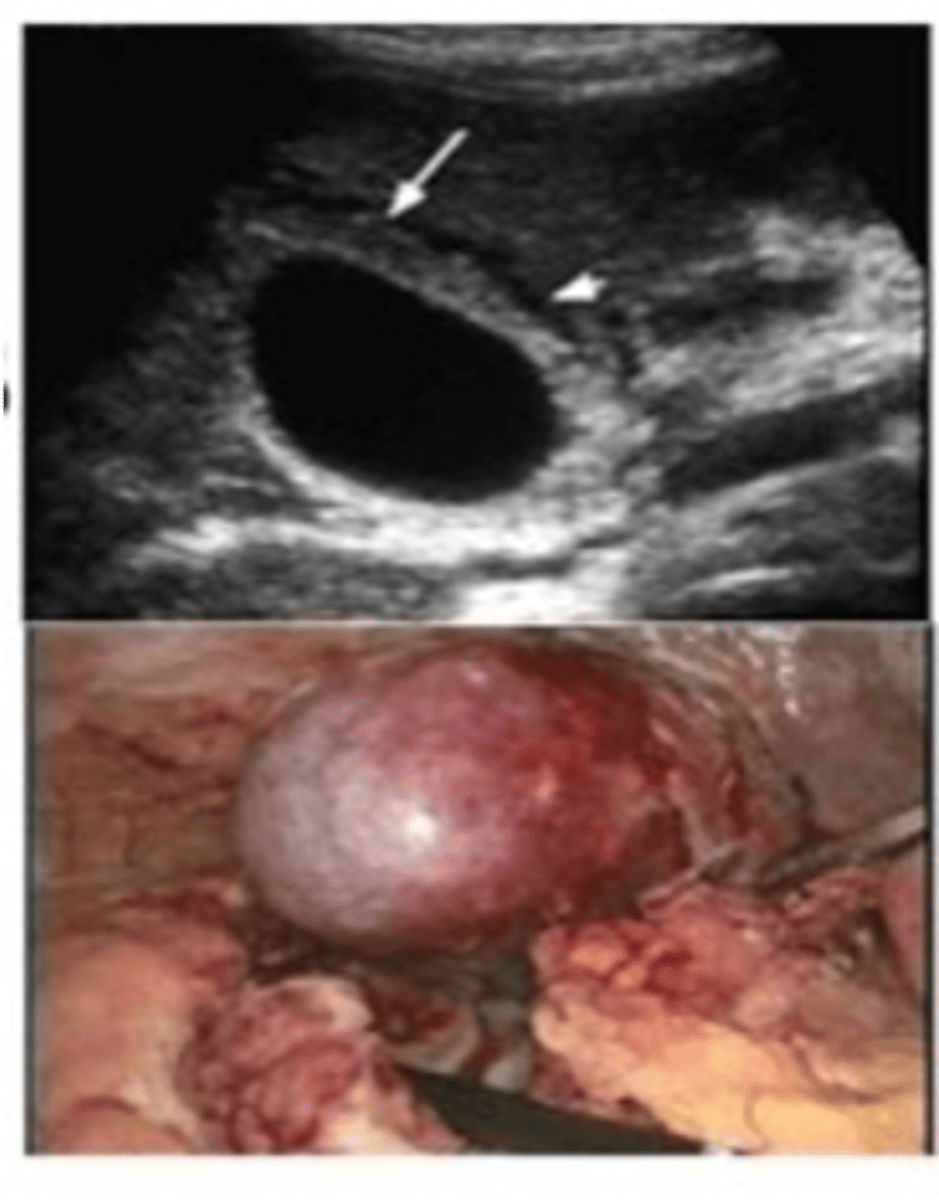

Pancreatic Pseudocyst

Define Condition:

Encapsulated collection of fluid formed by fibrous/granulation tissue surrounding liquefactive necrosis and pancreatic enzymes (no epithelial lining of cyst)

-Hx: Weeks after episode of Acute Pancreatitis

-Prog: Usually resolves spontaneously but may be infected & ruptured --> release of enzymes into abdominal cavity